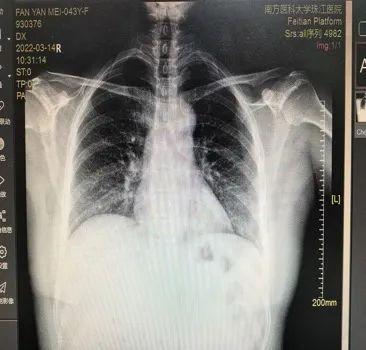

经过术前一周系统的心肺功能调整,2月17日,在全麻下王晓武主任团队给文先生进行手术,打开胸腔的那一刻,医生们吃了一惊:“这简直就是一颗‘牛心’!正常成人的心脏只有拳头大小,文先生的心脏有四五倍那么大,整个‘呼之欲出’。”

患者术前(左)与术后(右)心脏对比